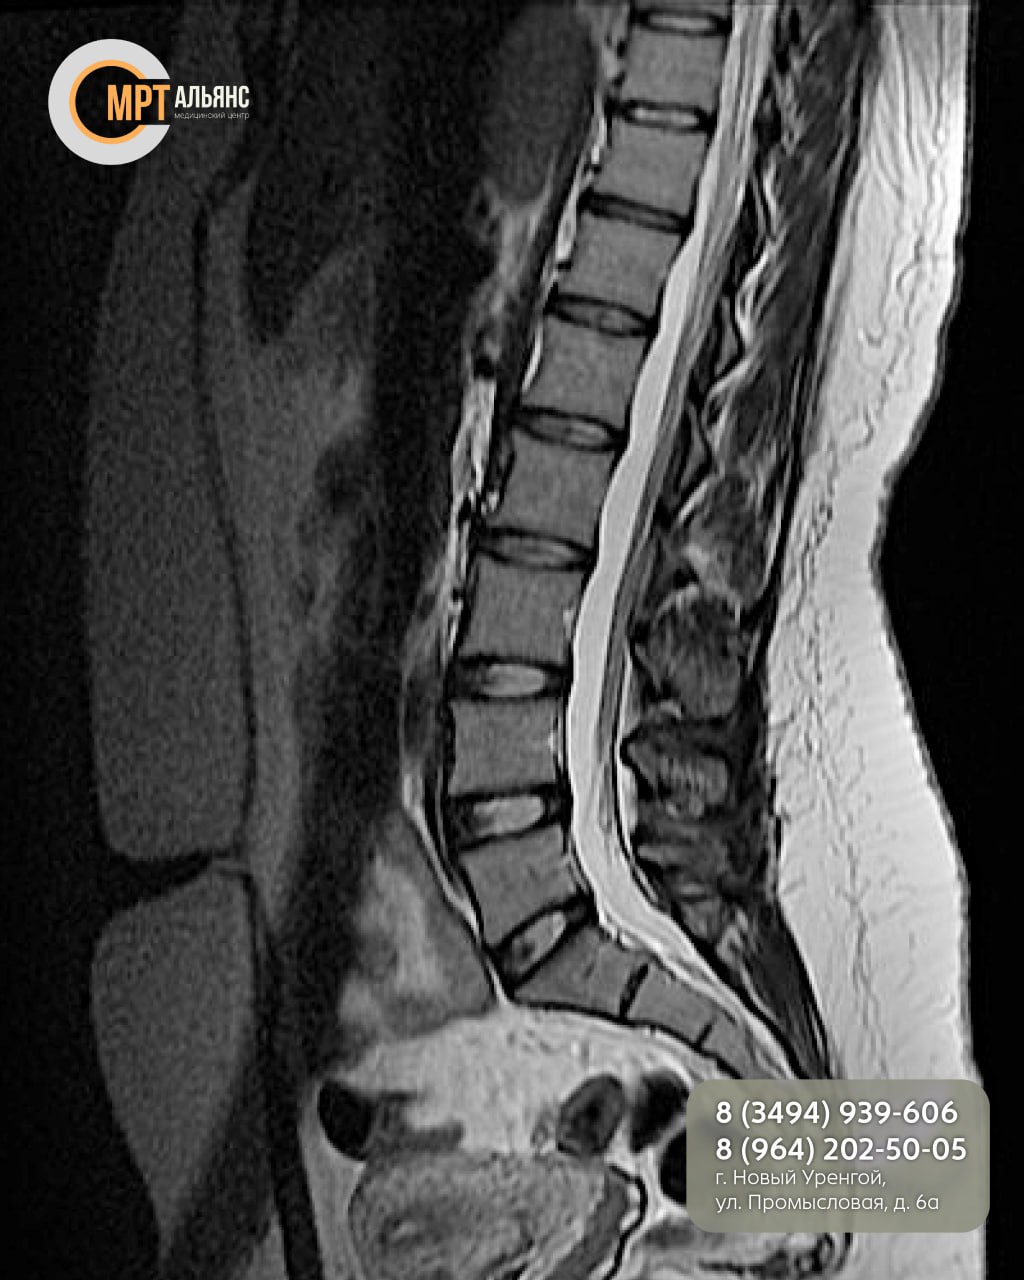

•Грыжи и протрузии межпозвонковых дисков

•Остеохондроз

•Травмы и смещения позвонков

•Артрит, артроз, стеноз

•Воспалительные процессы (болезнь Бехтерева)

МРТ идеально визуализирует мягкие ткани: спинной мозг, нервные корешки, межпозвонковые диски и связки. Идеально, когда КТ или рентген не дали четкой картины